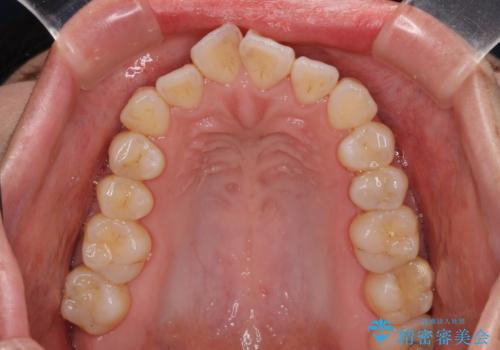

- 上下の出っ歯を気にして来院された患者様です。

口元を積極的に引っ込めるために、上下左右の第一小臼歯を4本抜歯することとしました。

また、上下前歯は舌の突出癖による開咬となっていたため、舌のトレーニングを徹底するよう指示しました。